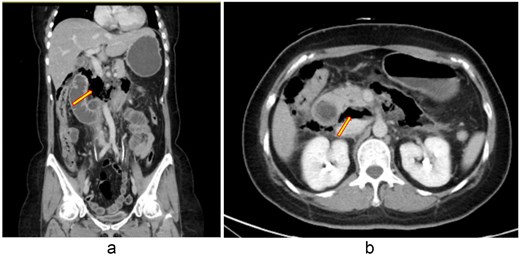

Laparoscopic lavage and abscess drainage yielded about 150 mL of turbid ascites in the subhepatic retroperitoneum without definite perforation, suggesting a sealed micro-perforation. The Estimated blood loss was 100 mL. Postoperatively, she received PCA, nasogastric drainage, parenteral nutrition, and antibiotics (cefazolin plus metronidazole, later flomoxef, then piperacillin–tazobactam). Persistent bilious drainage was noted. On postoperative day 2, she developed fever (38.4°C), leukocytosis (9790/μL), hypokalemia (2.7 mmol/L), and elevated CRP (154 mg/L). Despite therapy, bile leakage and right upper quadrant pain persisted. Follow-up CT on 2 September 2025 revealed probable perforation at the third portion of the duodenum with retroperitoneal abscess (Fig. 2). At her request, she was transferred to our hospital for further surgical management.

(a, b) Contrast-enhanced abdominal CT scan (coronal and axial views, 2 September 2025). Imaging demonstrates extraluminal air bubbles and a retroperitoneal abscess (arrow) adjacent to the third portion of the duodenum, consistent with duodenal perforation.